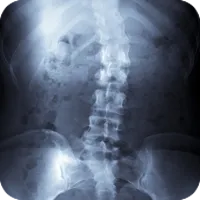

Scoliosis is a sideways curve of the spine that causes stiffness and pain. People with scoliosis have a sideways curve in their spine that makes an "S" or "C" shape.

Scoliosis is derived from the Greek term meaning curvature. People with scoliosis have a sideways curve in their spine that makes an "S" or "C" shape. The vertebrae can rotate at the thoracic level of the spine causing this curve and resulting in a hump near the rib cage. If the curve is more than 60 degrees it is considered serious. Usually this curve makes the waist or shoulders uneven. And unlike the normal curvature of the spine, adjusting your posture will not correct the problem.